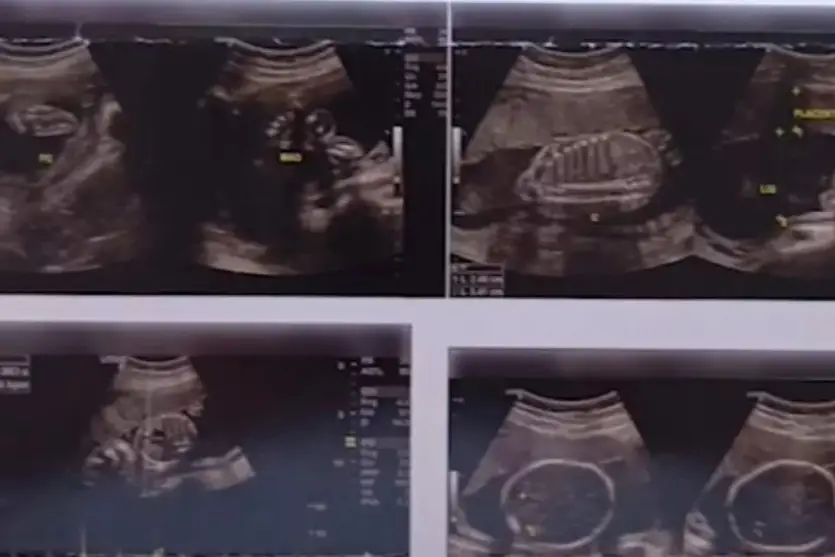

Um homem, de 48 anos, que realizou uma ultrassonografia abdominal para a identificação de hérnias teve um diagnóstico, no mínimo, inesperado ao obter o resultado dos exames. Ele, que fez o procedimento em uma clínica de Londrina, no Norte do Paraná, recebeu um laudo de gravidez, inclusive com imagens do bebê reveladas no exame.

“Fui fazer um ultrassom para ver duas hérnias, que é caso de operação. Só que chegou o resultado do exame e diz que eu estou grávido, vou ter um filho. No exame consta meu nome, tudo certinho, estou grávido”, disse o paciente.

A princípio a confusão se deu pela troca de imagens da ultrassom com o de uma mulher, que realmente estava grávidas. A clínica responsável pelo procedimento emitiu uma nota, nesta sexta-feira (20), onde diz que esse tipo de situação nunca havia ocorrido antes na clínica e que procurou o paciente assim que identificou que o resultado estava errado.